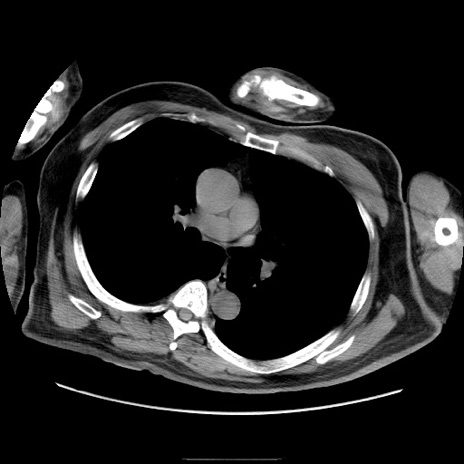

症例22(横断像)

【症例】50歳代男性

【主訴】腹痛

【現病歴】AVMからの被殻出血のため回復期リハ病棟入院中。 本日午後3時頃急に下腹部痛が出現した。

【既往歴】AVM、被殻出血、虫垂炎、高血圧

【身体所見】意識晴明、左半身不全麻痺、会話の理解は良好、36.5°C、腹部:膨隆、全体に板状硬、下腹部正中に圧痛点あり、反跳痛-、筋性防御不明、右下腹部にope scar

【データ】WBC 9400、CRP 0.06